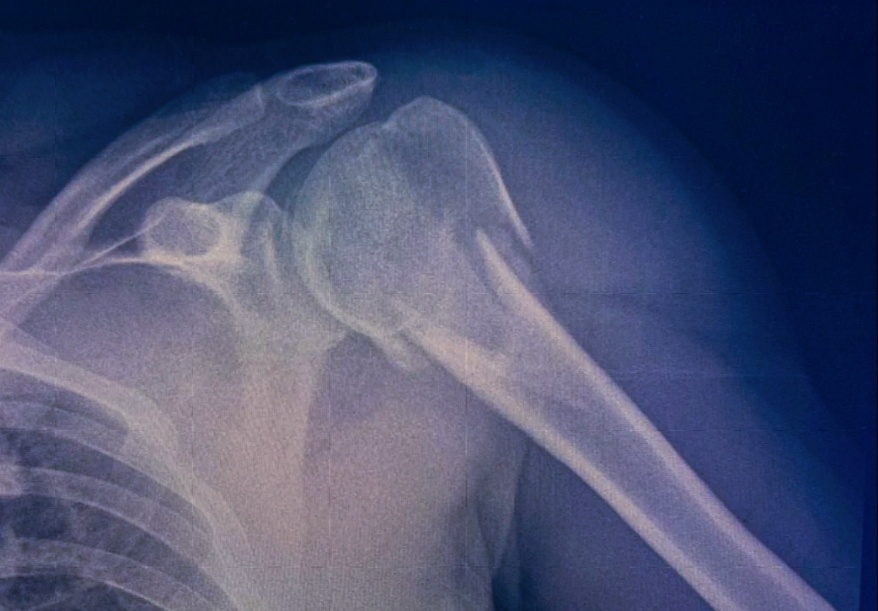

Назначили легкие, голову, кости таза, плечо, локтевой и коленный суставы.

Из всего назначенного и сделанного видно было , что сломано плечо и обе берцовые кости.

Потом посмотрела, что у нее по КТ определили линейный перелом левой височной кости с образованием гематомы, а так же сломанный кресцово-поясничный отдел.